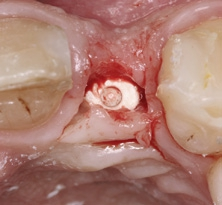

Der klinische Befund zeigte eine definitive Versorgung auf 12 und eine temporäre Versorgung auf 22. Dahingegen lag bei der Implantatversorgung in regio 22 der Verdacht auf eine partielle Fibro-Osseointegration vor (Abb. 1 und 2) [9,10].

Die partielle Fibro-Osseointegration, auch als aseptische Lockerung bezeichnet, ist ein Faktor für die verkürzte Lebenszeit eines Implantats [11]. Ursächlich dafür können mehrere Mechanismen sein: zum einen die Reduktion der Knochendichte in der Nähe des Implantats, verursacht durch eine veränderte Lastübertragung (sogenanntes „stress shielding“), zum anderen Mikrocracks im Implantatkörper, hervorgerufen durch beispielsweise zu hohe Kraftübertragung beim Eindrehen des Implantats.

Der chirurgische Eingriff wurde unter Lokalanästhesie mit palatinaler und labialer Infiltration durchgeführt. Zuerst erfolgte die Entfernung des Implantats. Für die Explantation wählten wir das aus unserer Sicht knochenschonendste Verfahren. Mithilfe einer Extraktionszange und mit entsprechend dosierter Kraft drehten wir das teilweise ankylotische Implantat in Achsrichtung aus, um auf jeden Fall die dünne labiale Knochenlamelle zu erhalten (Abb. 3). Dabei frakturierte der osseointegrierte Implantatapex tief im Implantatbett (Abb. 4). Um diesen zu entfernen, musste ein minimalinvasiver apikaler Zugang geschaffen werden. Nach einer krestalen Inzision mit mesialer Tunnelpräparation und distaler Entlastungsinzision sowie der Präparation eines Mukoperiostlappens zeigte sich ein ausgeprägter konkaver Alveolarknochen. Mit einem piezotechnisch unterstützten Chirurgieansatz fenestrierten wir die labiale Knochenlamelle (Abb. 5). Durch diesen minimalinvasiven Zugang lösten wir die ankylotische Verbindung und entfernten den apikalen Implantatrest. Bei dieser Methode der Implantatentfernung wird der periimplantäre krestale Knochen weitestgehend geschont.